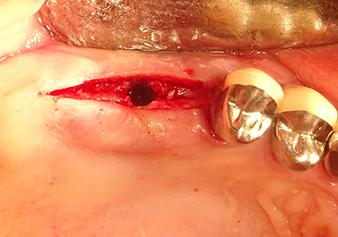

A 49-year-old female patient, a non-smoker and with nothing remarkable in her general medical history, was referred to our oral surgery practice for surgical extraction of tooth 16 and subsequent implantation. After the extraction, the patient experienced mild sinusitis trouble with the resultthat we initially waited six months before carrying out the measure. The residual bone height at the planned implant position measured 3-4 mm (Fig. 1 and 2).

Preoperative findings: The alveolar ridge has healed well, including sufficiently broad, keratinised gingiva

Fig.1: Preoperative findings: The alveolar ridge has healed well, including sufficiently broad, keratinised gingiva.

Following atraumatic preparation of the mucoperiosteal flap, the implant position was marked with the I1 instrument and the site prepared – until initial resistance was felt. Piezosurgical instruments were used in an up and down movement without any pressure being exerted. The piezoelectric vibration produced the desired and efficient cavitation.